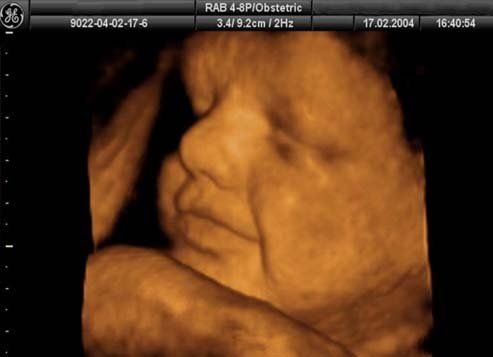

Elige cuando quieres hacer tus dos ecos de embarazo, y llévate tu ECOGRAFÍA EN 3 Y 4 D a partir de la semana 27, realizada por una DOCTORA EN GINECOLOGÍA Y OBSTETRICIA, que tiene la preparación profesional necesaria para advertirte de las posibles malformaciones o problemas que tu hijo pueda tener, y no sólo se limitará a grabarte en un soporte digital. Opta por la CALIDAD Y EL CONOCIMIENTO PROFESIONAL de la persona adecuada.

Podrás ver como se mueve, como se chupa su dedito, a quien se parece…. todo un mundo de sensaciones para disfrutar con tu pareja y/o con todas las personas que quieras que te acompañen para compartir ese momento tan especial, pues disponemos de una sala amplia para ello. Además te entregaremos en papel la fotografía más significativa de tu bebé.